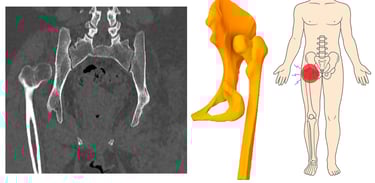

La cadera es vital para actividades cotidianas como trabajar, caminar y hacer ejercicio. Este estudio demostró la importancia de recopilar información sobre los tipos de cadera flotante para analizar la afección y establecer una metodología para el desarrollo de prótesis. Esta investigación facilita la creación de prototipos de prótesis de cadera debido a la complejidad y singularidad de las intervenciones necesarias, que pueden variar según la zona de las lesiones, que se producen ipsilateralmente y en dos huesos diferentes.

Radiografía de fractura de cadera y su localización.

Estos casos ayudan a desarrollar modelos de prótesis y a evaluar causas como accidentes, edad y sexo. Con base en estos resultados, se pueden presentar técnicas para el desarrollo de prótesis personalizadas. El trabajo futuro incluirá validación experimental y ensayos clínicos para evaluar la viabilidad y la eficacia del marco protésico propuesto. Al abordar los desafíos biomecánicos asociados con las lesiones de cadera flotante.